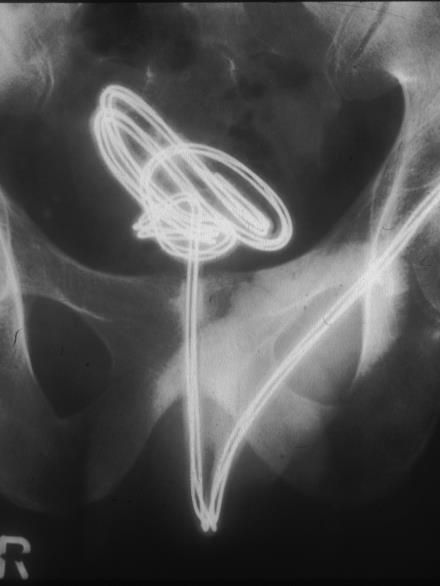

Die Urethra wird am häufigsten bei autoerotischen Aktivitäten verletzt. Betroffene führen unterschiedliche Fremdkörper in die Harnröhre ein, um die transurethralen Sexualrezeptoren zu stimulieren. Dabei kommt es entweder zur direkten Perforation der Harnröhre, meist im bulbären Bereich, zur Blasenperforation oder auch zu spezifischen Komplikationen, wenn sich z. B. ein Kabel verknotet oder ein Gegenstand zerbricht. Meistens gelingt eine minimalinvasive endourologische Lösung des Problems. Mitunter muss aber auch operativ interveniert werden. In unserer Klinik mussten wir zum Beispiel einmal ein zerbrochenes Reagenzglas in mehreren Teilen aus der Urethra bergen, wobei die Glasteile sehr schwer mit der Fasszange zu greifen waren. In einem anderen Fall mussten wir einen Bleistift, der transurethral eingeführt die Harnblase perforiert hatte, mit einem Holmium-YAG-Laser zerlegen, um ihn herauszuholen.

Die Urethra wird am häufigsten bei autoerotischen Aktivitäten verletzt. Betroffene führen unterschiedliche Fremdkörper in die Harnröhre ein, um die transurethralen Sexualrezeptoren zu stimulieren. Dabei kommt es entweder zur direkten Perforation der Harnröhre, meist im bulbären Bereich, zur Blasenperforation oder auch zu spezifischen Komplikationen, wenn sich z. B. ein Kabel verknotet (Abb. 1) oder ein Gegenstand zerbricht.